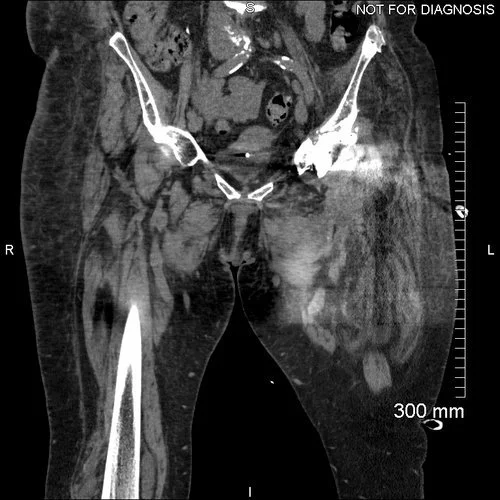

June’s case and imaging were reviewed by the infection Multi-Disciplinary Team (MDT). They diagnosed an infected left total hip replacement with massive soft tissue destruction. The challenge was to achieve a stable hip, free of infection and without dislocation (despite severe destruction of all proximal thigh muscles).

“June showed massive soft tissue destruction due to a previous metal debris inflammatory reaction. Further revision risked instability and she managed to cope without 20cm of proximal femur and skeletal traction for three months before her definitive operation.

Extreme soft tissue instability requires very good acetabular fixation, which can be more easily achieved with a custom-made implant.”